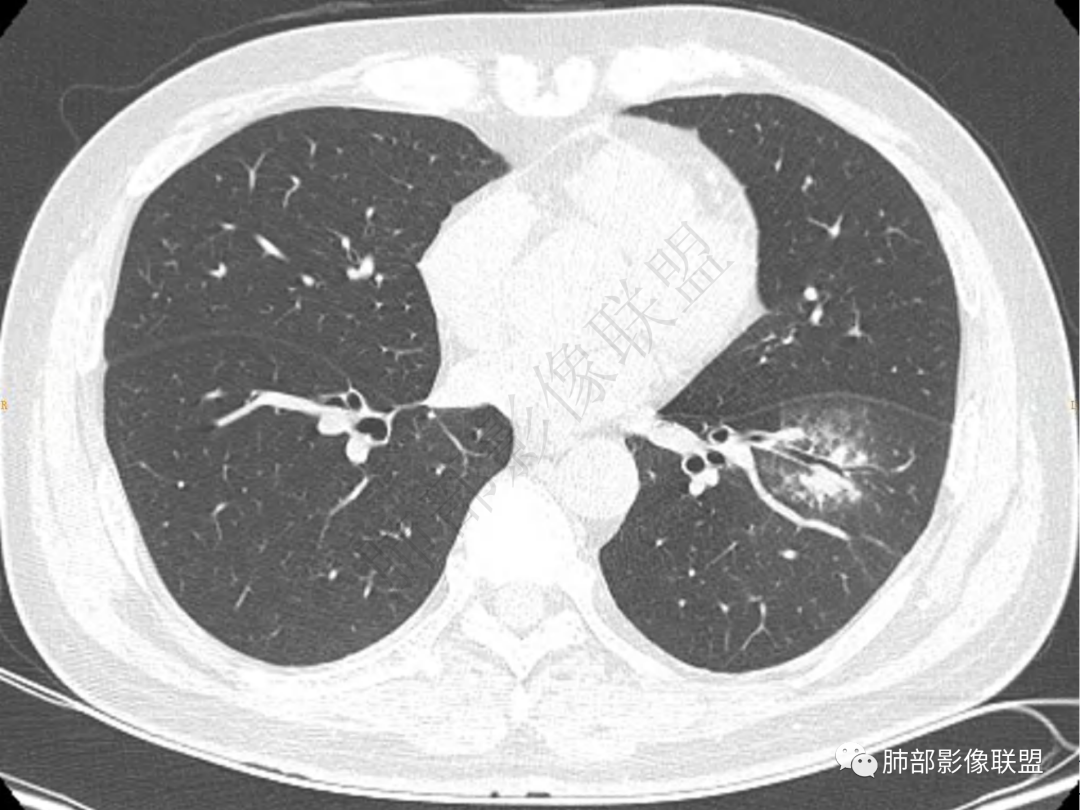

1.中年男性,咳嗽咳痰20余天,间断咯血2周

2.左肺下叶团片影,跨背段及内前基底段,实性部分类椭圆形,密度不甚均匀,可见毛刺及棘状突起,未见典型分叶及胸膜凹陷。病灶上下缘可见相应肺段支气管旁进侧出,管壁轻度增厚,未见狭窄阻塞。

3.周边较大范围磨玻璃影,边界相当模糊,小叶增厚明显。注意叶裂另一侧、左肺舌段亦可见磨玻璃影及增厚的小叶间隔。未见明确卫星病灶。

1.病灶不够密实,没有典型分叶,收缩乏力等,支气管未见截断等,缺乏一般肿瘤性肿块特征。

2.周围磨玻璃影边界不清缺乏限制,甚至“激惹”到相邻肺叶,也许提示较明显的炎性水肿。

正如多数老师分析到的,本例病灶炎性特点比较明显。